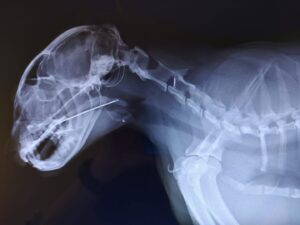

Kontrolliert man selbst die Mundhöhle seiner sich auffällig verhaltenden Katze, dann immer auch UNTER die Zunge schauen! Mit eine der häufigsten oralen Fremdkörper bei der Katze sind Fadenschlingen, die sich um den Zungengrund geschlungen haben und teilweise tief ins Zungenbändchen einschneiden. Aber auch in die Zunge, den Gaumen oder den Rachen eingespießte Nähnadeln sind nicht wirklich selten. Für die beiden Nadel-Fotos bedanke ich mich bei zwei Kolleginnen, die diese über eine entsprechende Fachgruppe zur allgemeinen Verwendung geteilt haben.